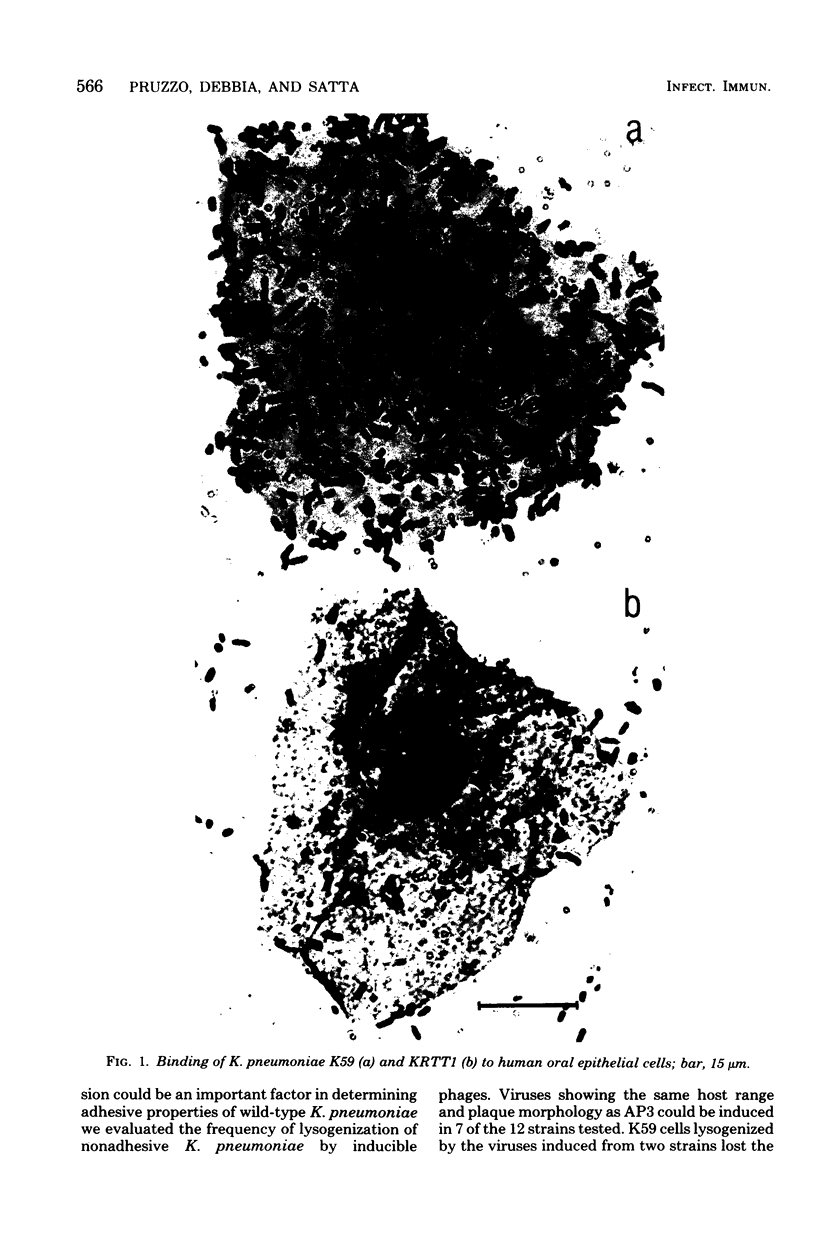

We have studied the adherence of both laboratory and wild-type Klebsiella pneumoniae strains, isolated from sputum, urine, and stool samples, to human buccal and intestinal and urinary tract epithelial cells. Of 32 unencapsulated strains, 30 adhered to all epithelial cells tested. Four K. pneumoniae strains lysogenic for AP3, a phage which causes conversion to resistance of coliphages T3, T7, and phi I, were all unable to adhere to epithelial cells. One of these strains was cured from phage infection and became capable of adhering, Spontaneous mutants resistant to coliphage T7, as well as K. pneumoniae K59-sensitive cells preadsorbed with inactivated T7 particles, did not adhere to epithelial cells. All strains capable of adhering were able to adsorb coliphage T7 and T3, whereas all nonadhesive strains were not. AP3-like prophages were induced from 7 of 12 nonadhesive Klebsiella strains. A laboratory strain which was able to adhere was lysogenized with 2 of these phages. In both cases, the strain lost its ability to adsorb coliphages T3, T7, and phi I and to adhere to human epithelial cells. All K. pneumoniae adhesive strains agglutinated yeast cells, whereas the nonadhesive strains did not. Competition studies have shown that D-mannose and concanavalin A prevented adherence to human epithelial cells, yeast agglutination, and adsorption of coliphage T7 to K. pneumoniae cells. It is concluded that in K. pneumoniae adherence to epithelial cells is mediated by the receptor for coliphages T7 (and T3), which in turn recognizes D-mannose in the receptors it binds.